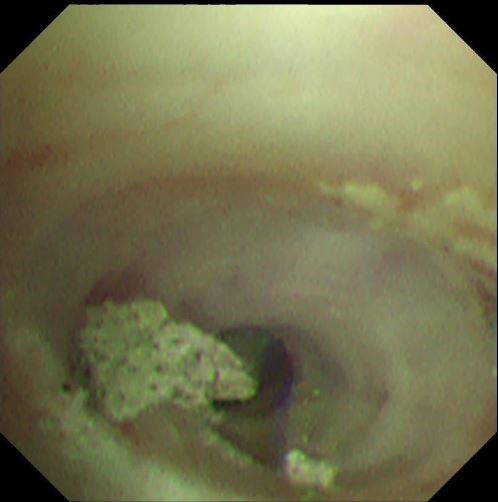

两天后复查支气管镜,发现患者左下叶背段远端细支气管仍有残留泥沙样异物。团队采用超细支气管镜联合冷冻技术,通过冷冻探头将异物凝固,再用超细活检钳逐支清理,实现对远端气道的彻底清理,实现气道“零死角”。

(超细支气管镜见左下叶背段远端支气管泥沙样物质)